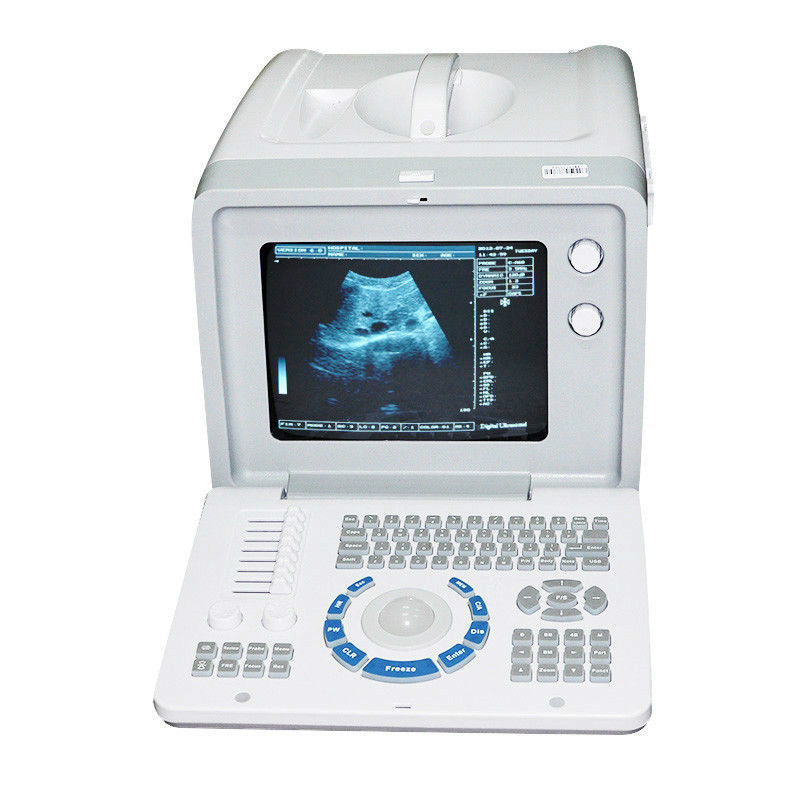

Advanced Imaging Technology

The Ultrasound Scanner utilizes cutting-edge imaging technology, allowing for detailed and accurate evaluations during pregnancy. With capabilities for both convex and transvaginal scanning, this device provides versatile options for healthcare professionals. It is essential for monitoring fetal development and ensuring the health of both the mother and the unborn child. Doctors can easily select the appropriate probe, enabling them to capture high-resolution images that are critical for diagnosis and treatment.

User-Friendly Features

One of the standout qualities of this Ultrasound Scanner is its user-friendly interface. Easy-to-navigate controls make the device accessible for both seasoned professionals and newcomers to the field. Additionally, the USB and VGA connectivity options facilitate quick data transfer and display on external devices, ensuring that vital information is readily available. Therefore, this Ultrasound Scanner not only performs well but is also designed with the user in mind, making it a suitable choice for clinics and hospitals.

Reliable and Affordable Solution

This Ultrasound Scanner represents a reliable and affordable solution for medical facilities seeking to enhance their diagnostic capabilities. By integrating advanced technology within an accessible price range, healthcare providers can perform qualitative screenings without overspending. As a result, facilities can increase their service offerings, provide better care for patients, and improve health outcomes. Invest in this state-of-the-art scanner and experience the benefits of enhanced prenatal care.